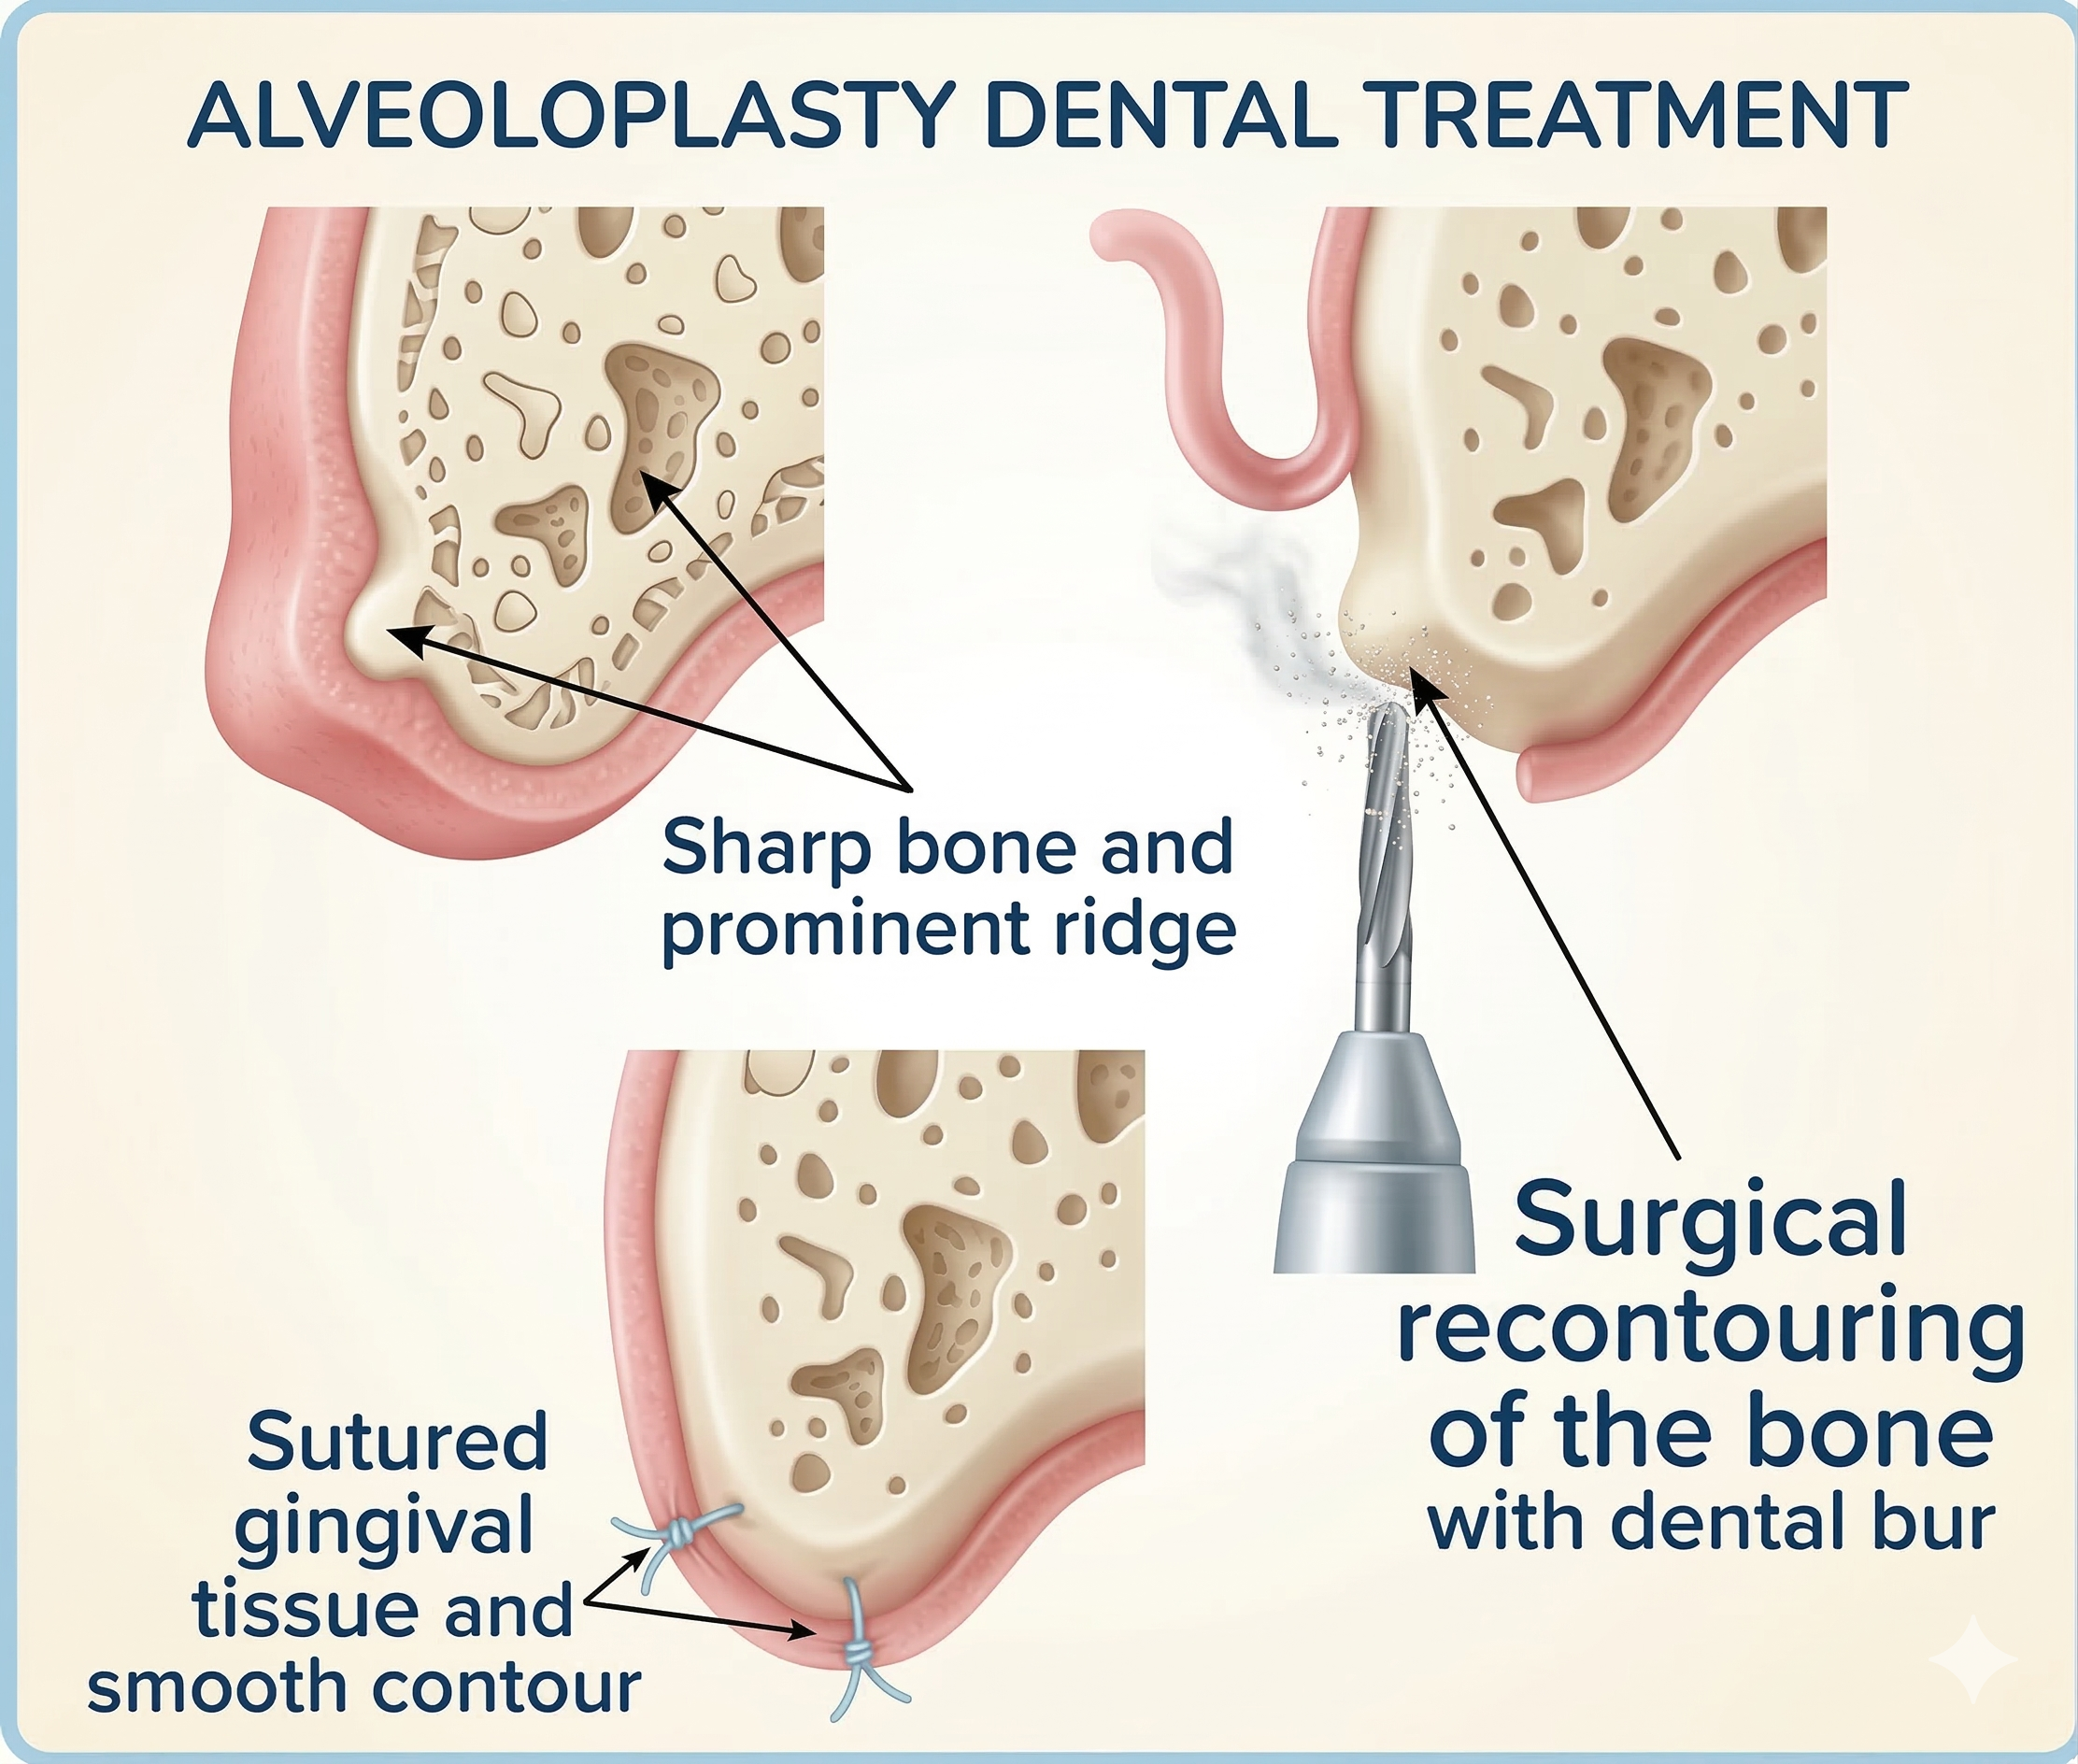

Alveoloplasty - Minor Surgery In Chennai

Alveoloplasty is a specialized minor surgical procedure used to smooth and reshape the jawbone (alveolar ridge), typically in areas where teeth have been extracted or lost. This procedure is essential for ensuring the jawbone is properly contoured to support dental implants, bridges, or dentures comfortably and securely.Alveoloplasty minor surgery is available at Best Dental Clinic – Dr N Deenadayalan T Nagar, Chennai and Dr Julian’s Laser Dental Clinic, Tambaram Chennai.

When is Alveoloplasty Needed?

While the jawbone naturally heals after an extraction, it can sometimes leave behind sharp edges, uneven ridges, or bony bumps. Alveoloplasty is recommended to:

-

Prepare for Dentures: Create a smooth, rounded surface so dentures fit snugly without causing painful sore spots.

-

Dental Implant Success: Ensure there is a flat, stable foundation of bone for precise implant placement.

-

Post-Extraction Healing: Smooth out sharp bone shards after a difficult or multiple-tooth extraction to speed up gum healing.

-

Correct Jaw Irregularities: Reshape the bone to improve the overall “arch” of the mouth for better aesthetics and function.